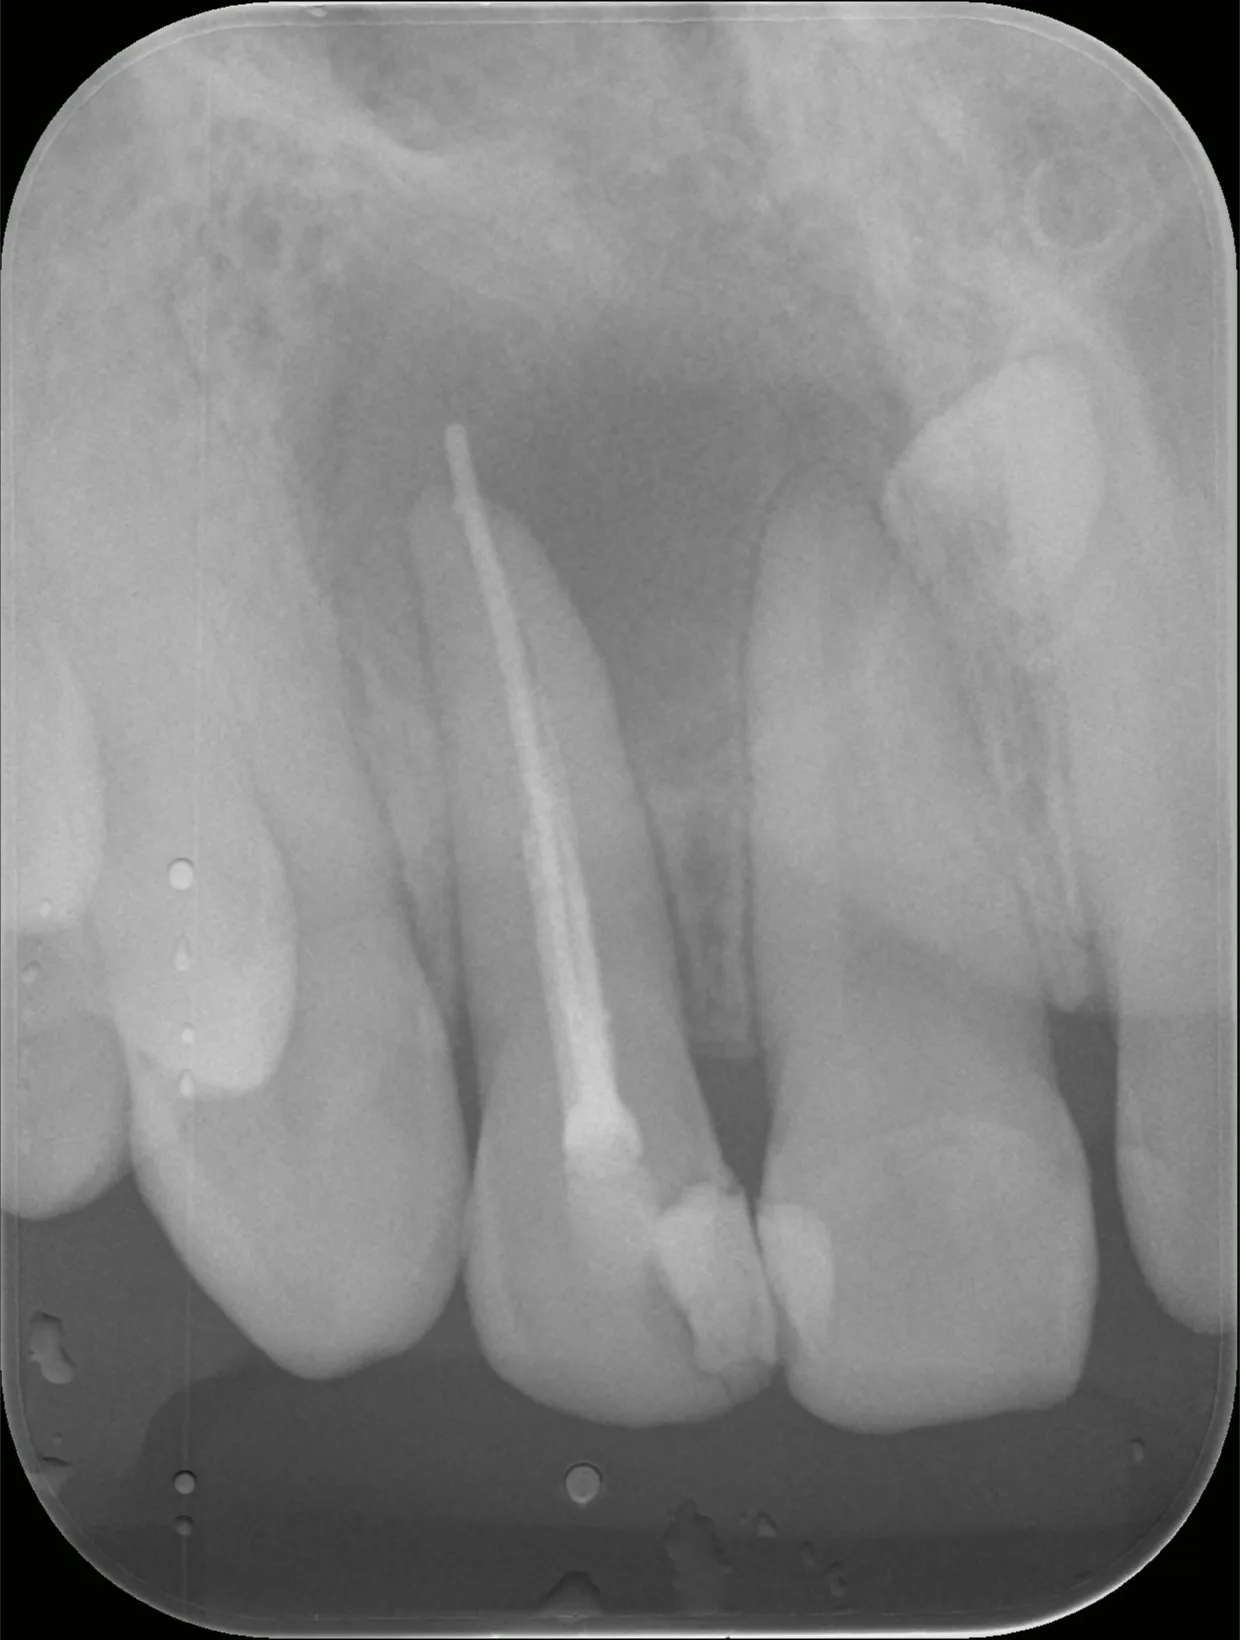

巨大な歯根膿瘍の根管治療1.5年経過症例

歯の根っこの先に膿ができる病気を歯根膿瘍、または袋状になった物を歯根嚢胞と言います。

今回は歯根膿瘍で上あごが大きく腫れてしまっていた状態の治療とその経過についてご紹介いたします。